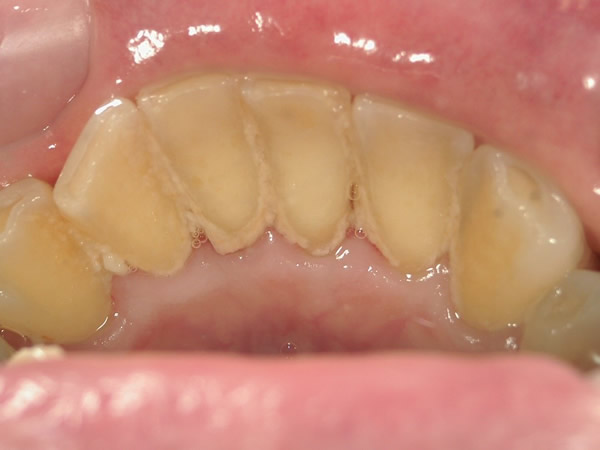

患者さんご自身にも現状を知っていただくために、お口の中を撮影します。歯並びや、かみ合わせ、磨き残しなど細かく記録し、治療後の変化等を評価します。